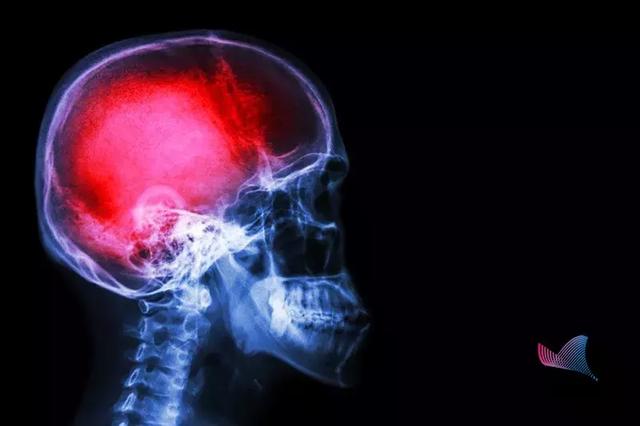

中風(fēng)

第一殺手,是造成中國人壽命損失的第一大病因。據(jù)WHO數(shù)據(jù)顯示,我國腦卒中的發(fā)生率位居世界第一。

我國每年腦卒中發(fā)生病例500余萬,其中約有196萬人死亡。

也就是說,

腦卒中

每6.2秒就有一人發(fā)生,每16秒就有一人死亡!腦卒中已成為我國居民死亡首要因素。更可怕的是,中風(fēng)不僅僅是老年人的專利,在我國

腦卒中,又稱中風(fēng),很多人對中風(fēng)的認識只是停留在患者會口眼歪斜、口齒不清。

什么是腦卒中?

當附著在血管壁的栓子脫落,堵塞腦部血管時,形成缺血性中風(fēng)。而當腦血管破裂,顱內(nèi)出血時,就會形成出血性中風(fēng)。